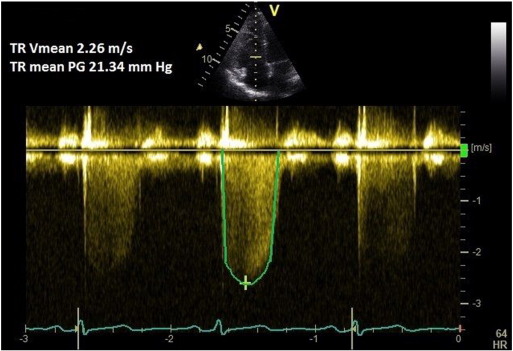

Continuous wave (CW) Doppler of the tricuspid regurgitation (TR) trace is used to measure the difference in pressures between the right ventricle and right atrium. The simplified Bernoulli equation (P = 4[TRmax]2 ) is used to calculate this pressure difference using peak TR velocity. This method correlates well with PASP on right heart catheterisation [6] and [7] . A peak TR velocity value of ≤ 2.8 m/s is considered normal.

A coaxial TR jet is identified in parasternal long axis (RV inflow), parasternal short axis, or apical 4-chamber view with the help of colour Doppler. CW Doppler is used with a sweep speed of 100 mm/s to achieve a satisfactory envelope (Fig. 1 ). The peak velocity of the envelope is then measured (TRmax ). A value of ≤ 2.8 m/s suggests low probability, a value of 2.9–3.4 m/s indicates intermediate probability, and a value > 3.4 m/s suggests a high probability for pulmonary hypertension [1] . Traditionally, right atrial pressure (RAP) is assumed by the size and distensibility of inferior vena cava (IVC) during inspiration at rest and during forced inhalation, and this value is added to the peak TR velocity [8] . However, recent ESC guidelines suggest just using the TRmax without additional RAP, as IVC assessment is error prone [1] . Mean PAP can be approximated from the systolic PAP (SPAP) using the following formula: mPAP = 0.61*SPAP + 2 mmHg [9] .

Fig. 1. TR Vmax method for measuring PASP. |